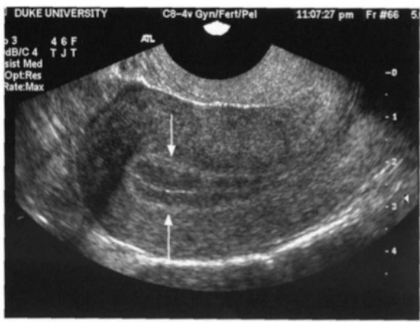

Identify the endometrial phase

Secretory phase: uniformly echogenic and thick